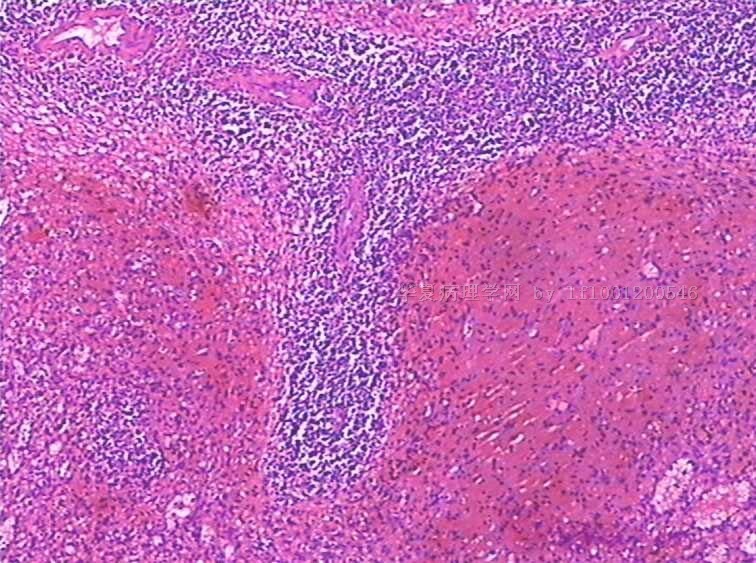

性别:

女

年龄:

49

标本名称:

反复发热,全血细胞下降1月余.CT示肝、脾肿大。骨髓检查:增生活跃,红系增高。

手术所见:脾巨大,内有梗死。肝表面光滑、肿胀。肝门淋巴结肿大,无腹水。

巨检:脾切除一个,20×15×8cm.切面灰红,有多个灰白区,最大8×6×3cm,呈楔性,小者绿豆大小

见到一些异型细胞,细胞质几乎看不到。考虑为淋巴造血系统肿瘤,脾脏原发淋巴瘤可能。

是好多组织细胞吗?期待中